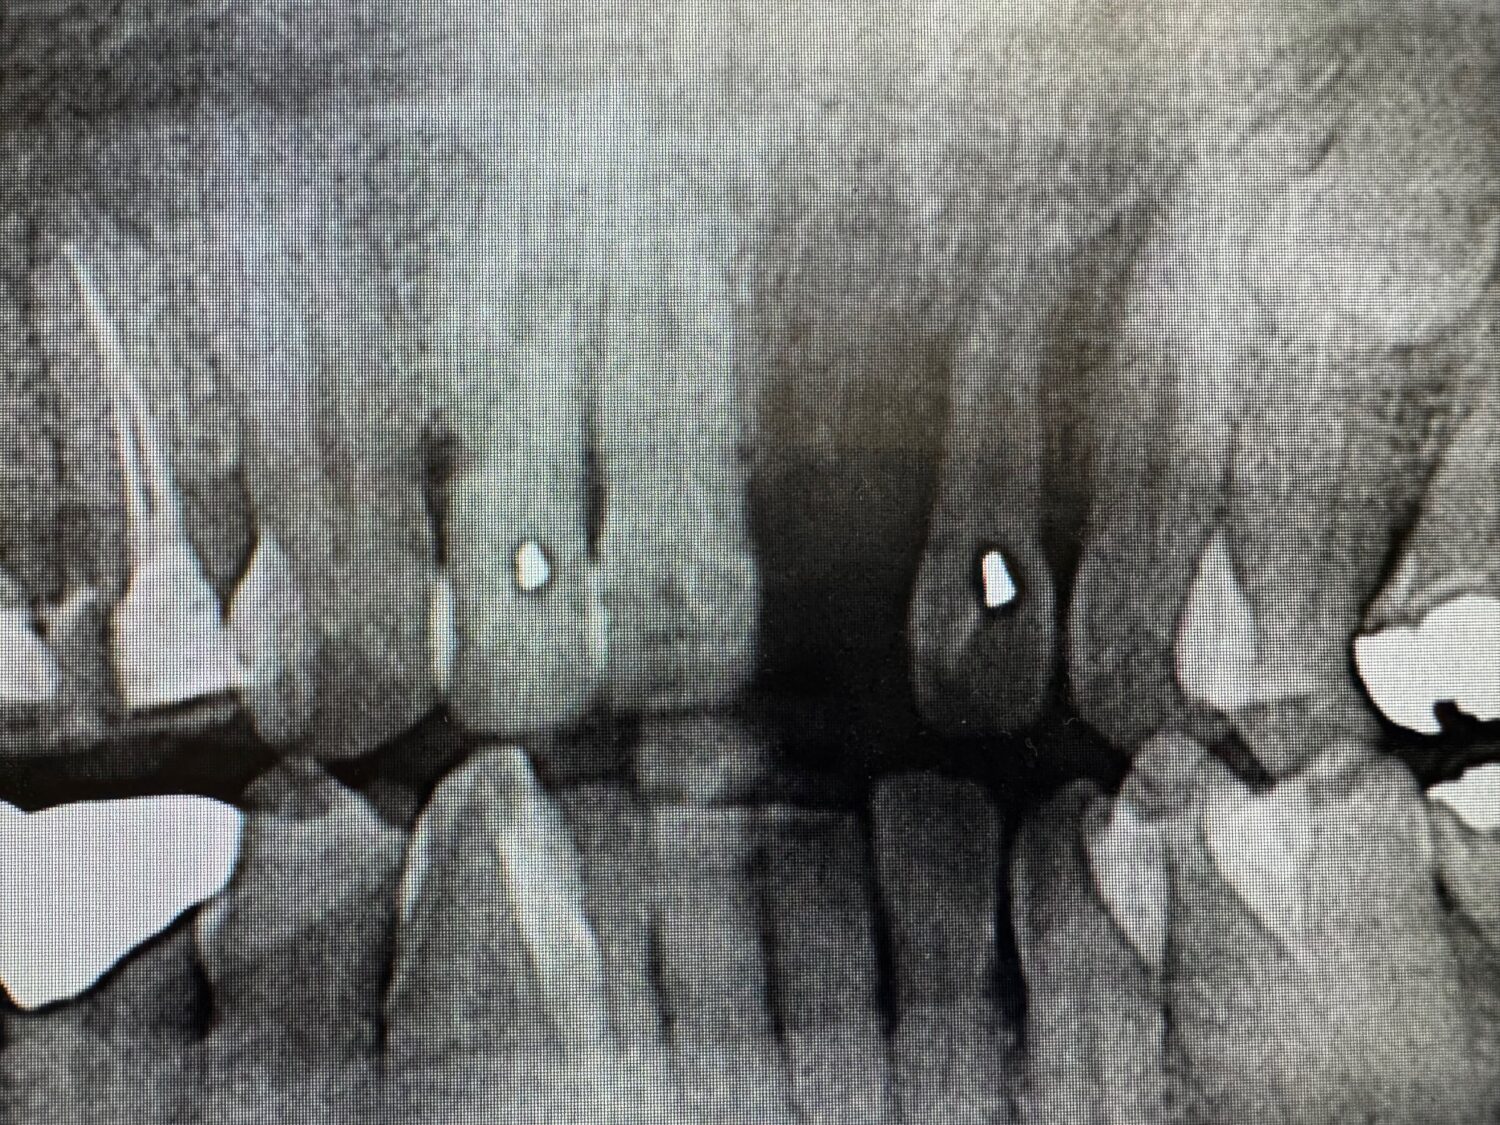

交通事故で前歯を1本失った方へのインプラント手術を行いましたこんにちは。岡山なかの歯科・矯正歯科クリニック院長の 中野浩…